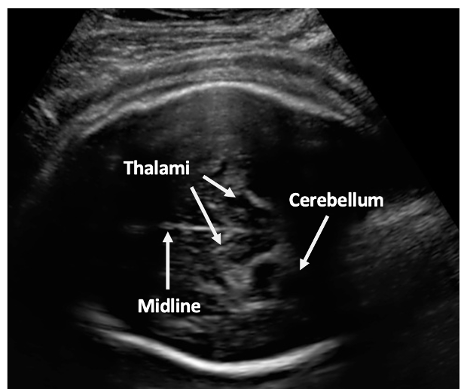

Intrapartum ultrasound in second stage of labour: determining prognostic factors for type of birth. We invite mothers to take part in our study that are having their first baby at term (37-42 weeks) and wish to have a vaginal (normal) delivery. We use ultrasound to assess which way the baby is positioned and also how low the baby’s head is in the birth canal. When the healthcare practitioner confirms the cervix (neck of the womb) is fully dilated (10 cm), we perform the ultrasound scan at this time. There are two ultrasound methods: transabdominal and transperineal. Transabdominal ultrasound scan is similar to scans that are done routinely in pregnancy, assessing the baby's position and function of the placenta.